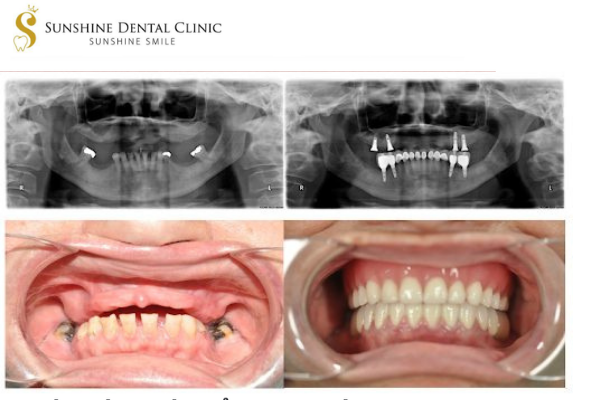

CẤY GHÉP IMPLANT TỨC THÌ RÚT NGẮN THỜI GIAN – TĂNG TÍNH AN TOÀN

1.IMPLANT NHA KHOA TỨC THÌ

Việc đặt implant sẽ được thực hiện trong vòng 24 đến 48h sau nhổ răng và người bệnh sẽ có răng mới để đảm bảo thẩm mỹ và việc ăn nhai hiệu quả.

2.ƯU ĐIỂM CỦA IMPLANT TỨC THÌ TRONG PHỤC HỒI RĂNG MẤT

Việc phục hình răng tức thì đối với các vùng thẩm mỹ như răng cửa, nhóm răng tiền cối có ý nghĩa rất quan trọng trong việc cải thiện thẩm mỹ, giúp người bệnh cảm thấy tự tin hơn trong công việc, giao tiếp với người khác